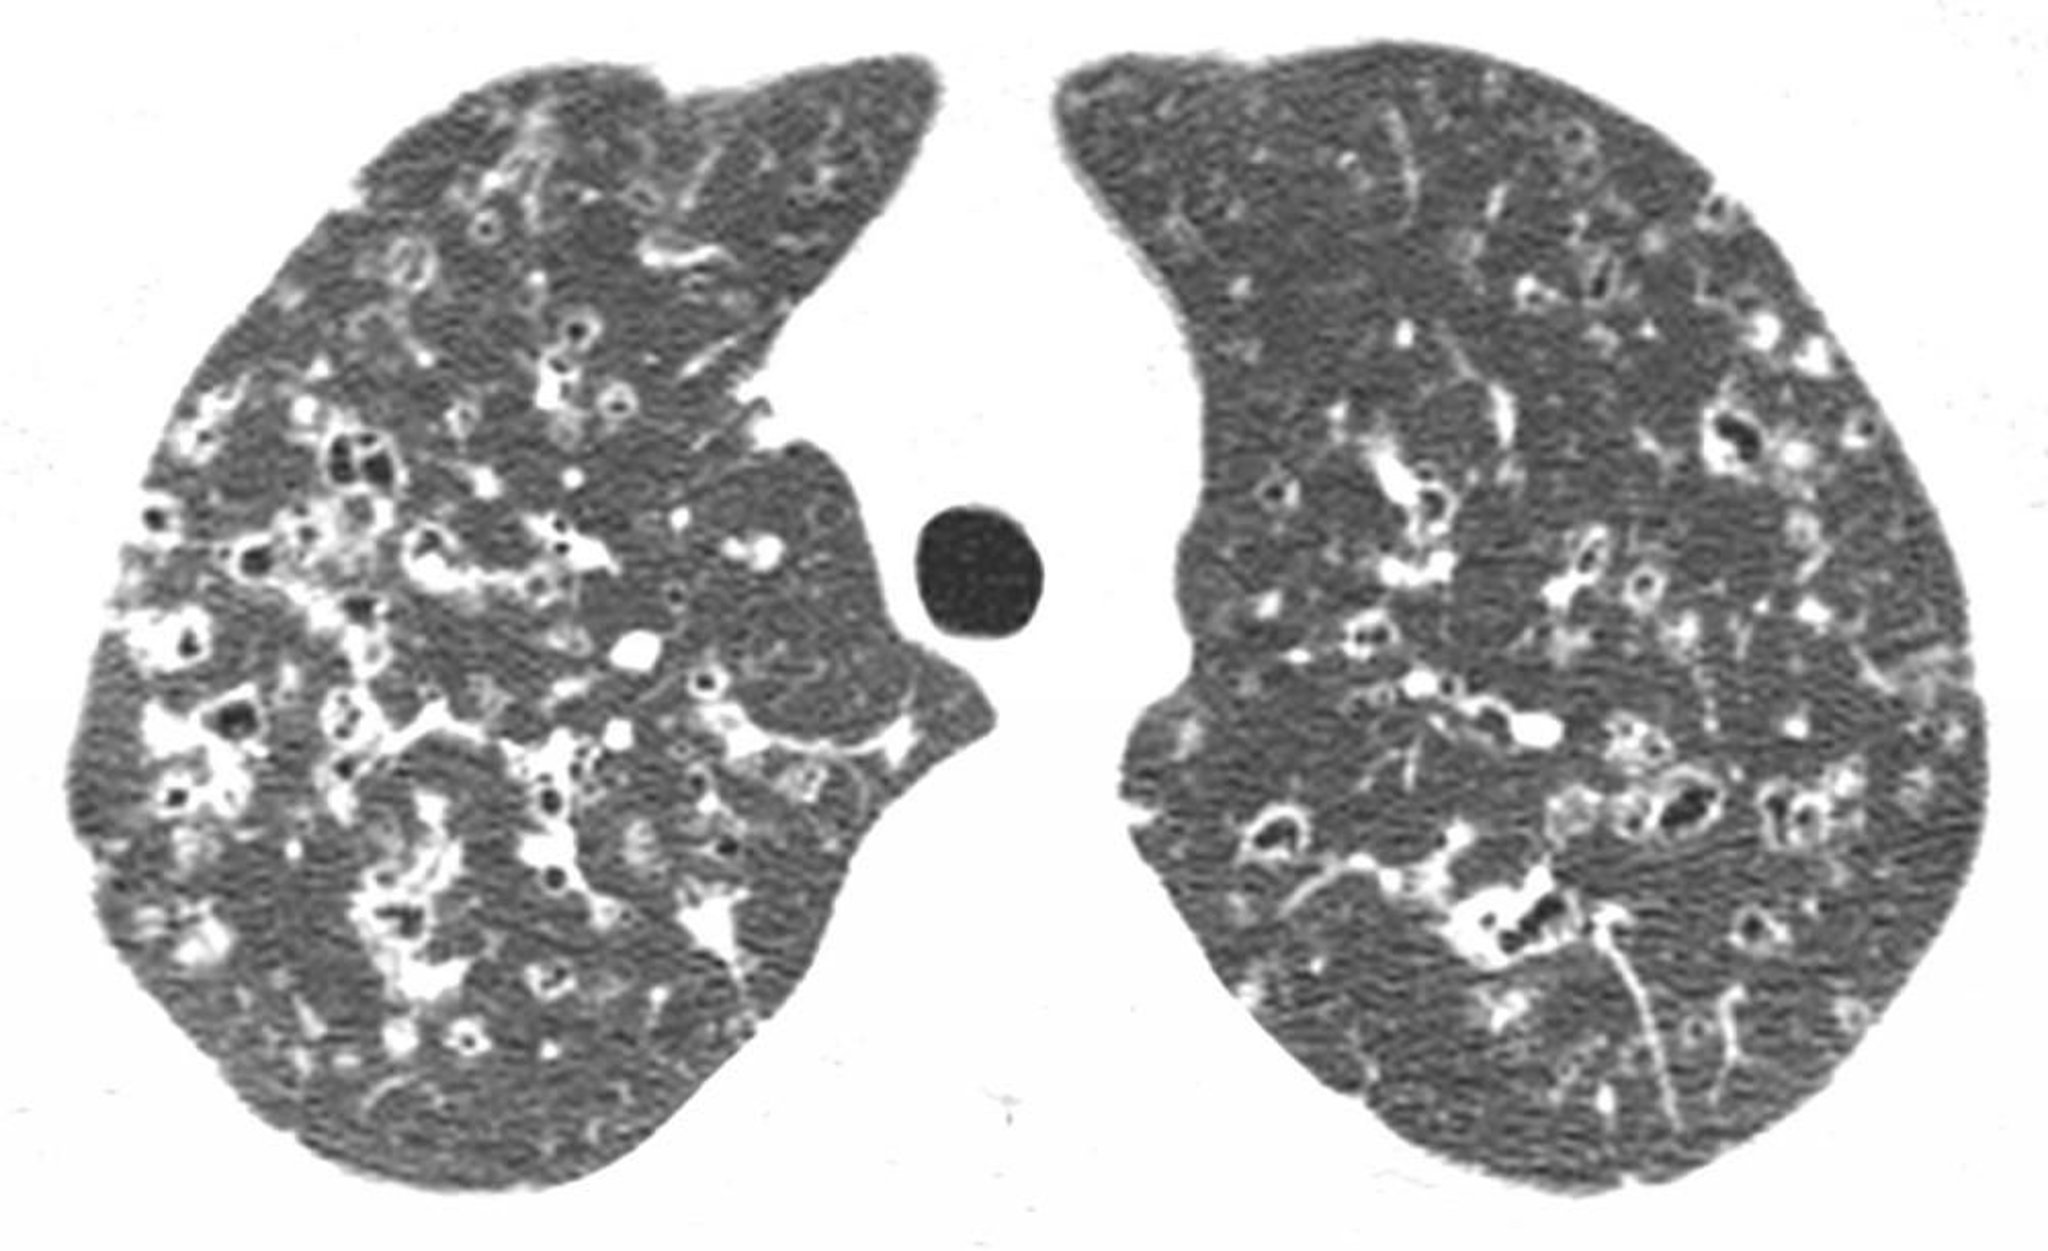

Istiocitosi polmonare a cellule di Langerhans

La TC ad alta risoluzione mostra noduli e cisti irregolari a densità d'aria nei lobi superiori, di solito nelle regioni superiore e medio-polmonare. Questi risultati sono caratteristici dell'istiocitosi a cellule di Langerhans in un paziente con storia di fumo.

Image courtesy of Harold R. Collard, MD.